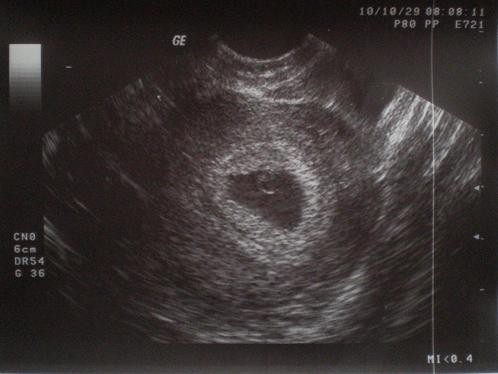

A sziámi ikrek a momo ikrek speciális válfaja vagyis különféle összenövésekre és változásokra kerülhet sor. Világszerte többféle módszert is alkalmaznak a magzati méretek számítására amelyek különböző nemzetiségű orvosok állítottak össze. A tudomány rengeteget köszönhet az ikervizsgálatoknak hiszen segítségükkel egy sor betegség kialakulását genetikai hajlam vs. 1 ha a szétválás a fogamzást követő néhány órán de maximum 2 3 napon belül történik akkor a szétvált zigóták már a petevezetékbe is külön külön vándorolnak majd a méhben külön ágyazódnak be.

Ez az esemény elég stabilan 4 arányú. Ebben az esetben a petezsák egy de magzatburokból kettő lesz illetve szeparáló hártya nő a gyerkőcök közé. Az egypetéjűeknek viszont azonos a génkészletük. Egy friss kutatás szerint az ikrek tovább élnek mint a többség és az egypetéjű ikrek még annál.